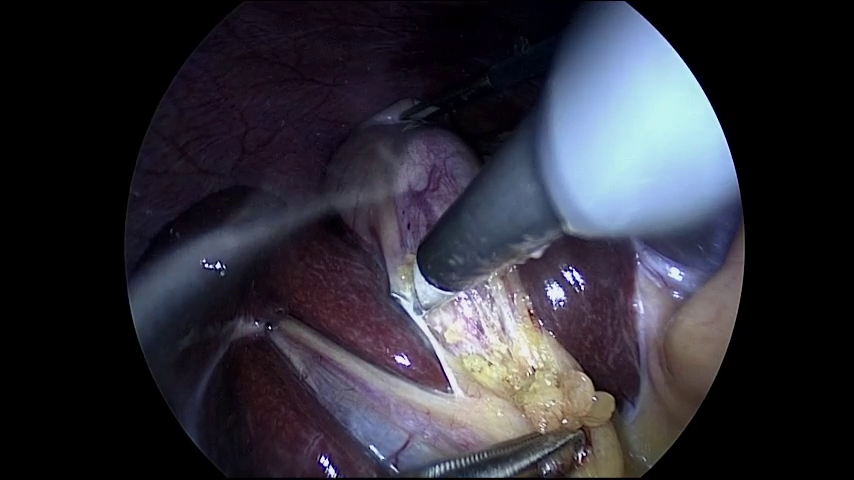

The subsequent step in the analysis of NeRV-S model was to train it using every second frame. This means that the analysed Cholec80 video was initially extended to 200 frames and was later compressed to 100 using every second frame. After the training, as it was expected, the final PSNR value for this case was lower compared to the subsequent 100 frames scenario. Nevertheless, the quality of the output images still remained very close to the ground truth as seen in Figure 7.

Figure 7: Ground truth (left) (Twinanda et al., 2017) and prediction (right) of NeRV-S (1200 epochs, trained on every second frame) for frame 10.